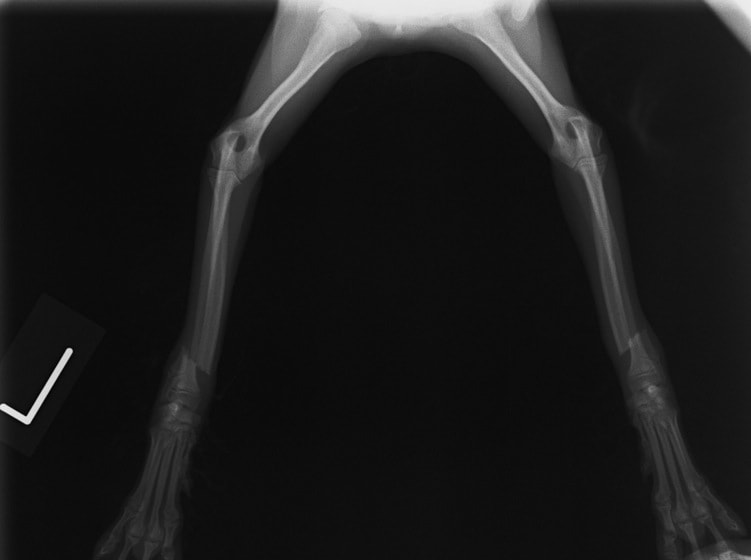

症例3:キルシュナーワイヤーのピンニングによる整復

ペルシャ猫 11ヶ月齢 雄

他院にて左大腿骨遠位の成長板骨折(salter-harrisⅠ型)が認められており、治療相談を目的として来院。当院にて、キルシュナーワイヤーを用いたピンニングにより骨折部位の整復を行いました。術後の経過は良好で、現在も経過観察中です。

術前レントゲン

術後レントゲン